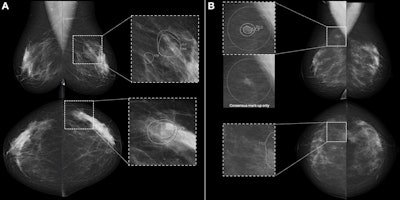

Full-field digital screening mammograms in participants recalled by the consensus discussion after being flagged by artificial intelligence (AI) computer-aided detection (CAD) but not by either of the two radiologists. (A) Mammogram with AI CAD score of 73 for a 55-year-old woman diagnosed with grade 3 in situ cancer and T1 (9-mm) invasive cancer in the left breast and lymph node metastasis. (B) Mammogram with AI CAD score of 54 for a 49-year-old woman diagnosed with grade 2 in situ cancer and T1 (6-mm) invasive cancer in the right breast and without lymph node metastasis. All images and caption courtesy of the RSNA.